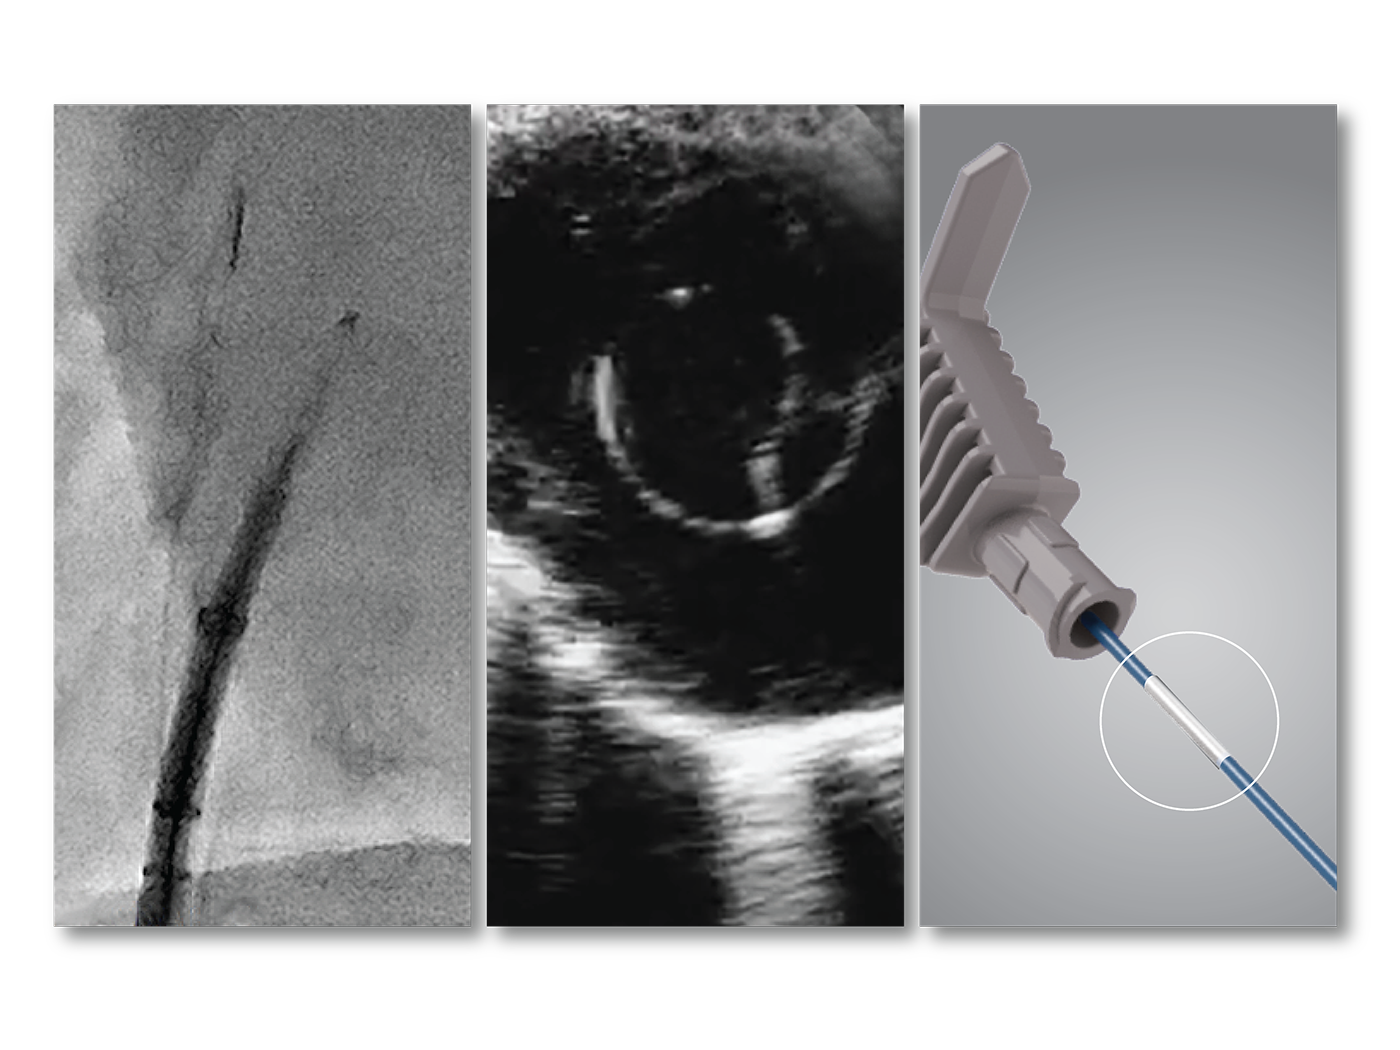

Know where you are at all times with OMNIviz technology

Reliably locate the VersaCross Connect solution on fluoroscopy and ultrasound. Positional markers indicate position of RF tip within dilator. Connect to DuoMode Cable to track and mark RF tip on mapping system.

Fluoroscopic image of RF wire in sheath/dilator assembly.